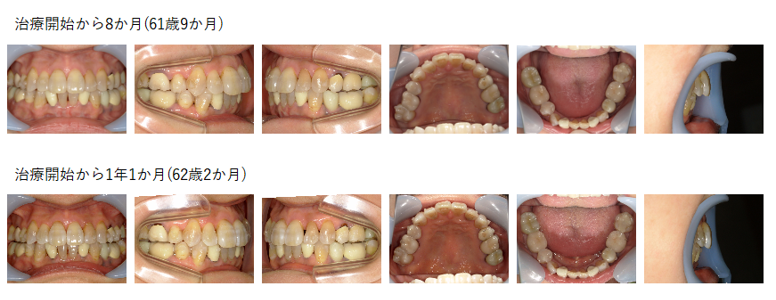

【治療例 K8301】初診時年齢:61歳0か月 / 性別:女性 / 主訴:上前歯が出てきた、下のガタガタ

治療の概要:45年前に名誉院長が上下顎両側第一小臼歯を抜歯をした症例であるが、上下顎前歯部に後戻り(叢生)が認められた。隣接歯面の削合を行いながらマウスピース型(アライナー型)矯正装置(インビザライン®)にて叢生の改善を行った。

主訴:上前歯が出てきた、下のガタガタ

診断名:上下顎両側第一小臼歯の既抜歯を行っていた後戻り症例

使用した主な装置:マウスピース型(アライナー型)矯正装置(インビザライン®)

抜歯/非抜歯および抜歯部位:非抜歯(上下顎両側第一小臼歯の既抜歯)

※こちらの症例は2022年6月から2025年12月に行った矯正です(2023年12月~は保定期間)

治療期間:3年6か月

治療回数:28回

アライナー枚数:初回31枚+追加①10枚 合計41枚使用